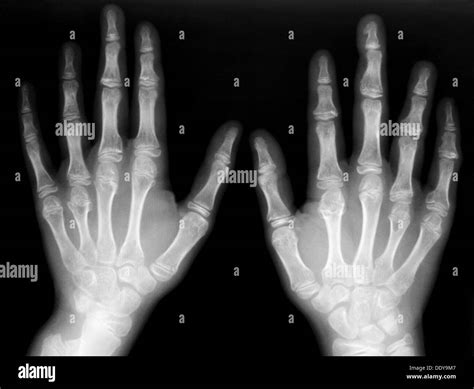

A Hand X Ray is a non-invasive diagnostic procedure that uses a small, controlled amount of ionizing radiation to create images of the bones within the hand. The human hand is a complex structure consisting of 27 distinct bones, including the carpals of the wrist, the metacarpals of the palm, and the phalanges of the fingers. Because of this complexity, obtaining a clear image is essential for pinpointing the exact location of injury or disease.

During the procedure, the hand is positioned on an imaging plate. A beam of radiation is directed at the area, and because bone is denser than the surrounding soft tissue, it absorbs more of the radiation. This causes the bones to appear white on the image, while soft tissues appear in shades of gray, and empty space or gas appears black. This contrast allows medical professionals to assess structural integrity with high precision.

After the images are captured, they are reviewed by a radiologist—a physician specially trained to interpret medical images. They look for subtle signs of trauma or degeneration, such as:

- Bone Alignment: Checking if the bones are in their anatomical position or if a displacement has occurred.

- Cortical Integrity: Searching for breaks or "step-offs" in the outer layer of the bone.

- Joint Space: Evaluating the distance between bones to determine if cartilage has worn away.

- Soft Tissue Swelling: Sometimes, even if the bone is intact, the image will show swelling in the surrounding tissue that indicates a soft tissue injury.